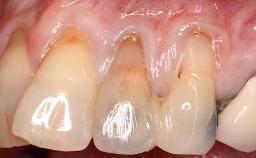

In 1983, a 51-year-old non-smoking patient was referred for the treatment of moderate chronic periodontitis. At the initial examination, 47% of sites exhibited probing depths of 4 to 6 mm. Periodontal therapy consisted of initial periodontal treatment including oral-hygiene instructions and supra- and subgingival debridement, followed by periodontal surgery to eliminate residual pockets.

| Soft Tissue Grafting | Simultaneous |